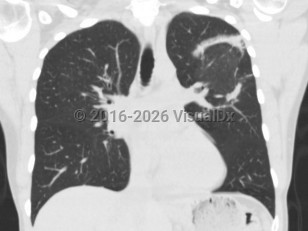

Imaging Studies image of Cryptogenic organizing pneumonia - imageId=8350008. Click to open in gallery.  caption: '<span>Reverse halo/atoll sign within  the right upper lobe and superior segment of the right lower lobe, with  peripheral dense airspace and central areas of ground glass  attenuation. Some additional areas of ground glass and airspace  opacities, and patchy airspace disease with the right middle lobe, with  traction bronchiectasis and architectural distortion.</span>'

Reverse halo/atoll sign within the right upper lobe and superior segment of the right lower lobe, with peripheral dense airspace and central areas of ground glass attenuation. Some additional areas of ground glass and airspace opacities, and patchy airspace disease with the right middle lobe, with traction bronchiectasis and architectural distortion.